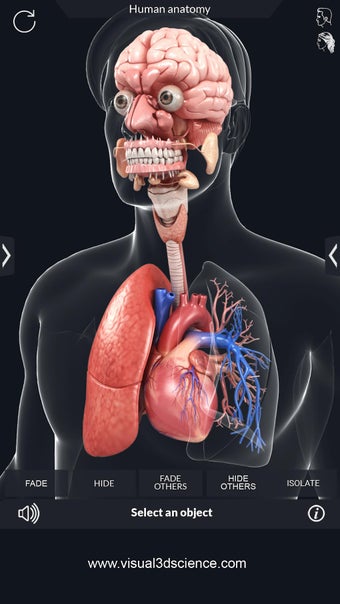

Met deze applicatie kun je 360° draaien rond een zeer realistisch 3D-model van het menselijk lichaam. Je kunt in- en uitzoomen op elk deel om er beter naar te kijken.

De camera kan worden verplaatst om een ander beeld van elk deel te krijgen.

Het is zeer eenvoudig te gebruiken en kan een zeer nuttige applicatie zijn voor iedereen die het menselijk lichaam moet bestuderen.